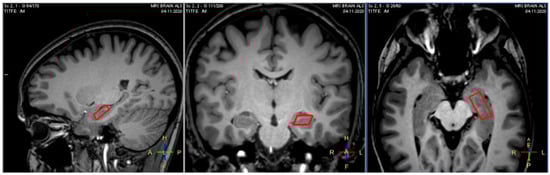

2.5. MRI Data Analysis

2.5.2. Hippocampal GM Analysis